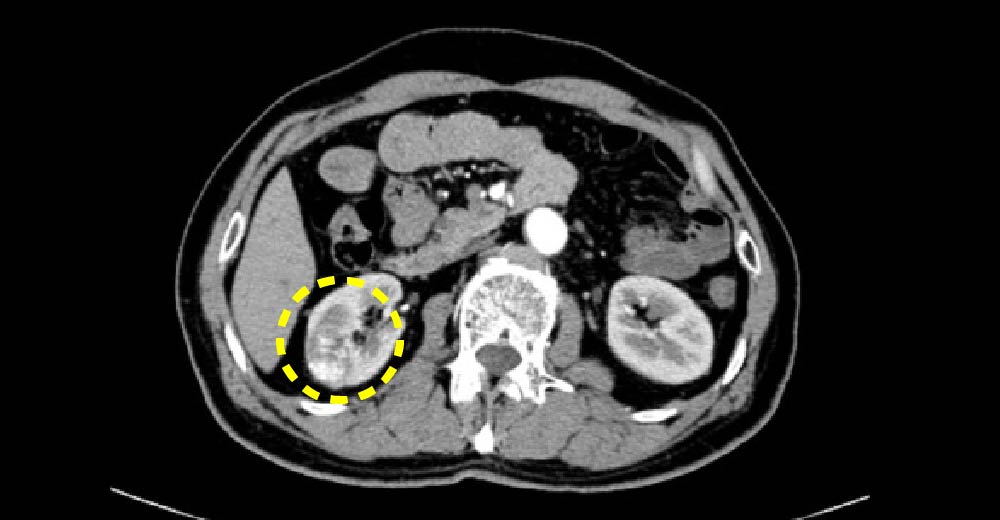

腎細胞がん

腎細胞がん症例です。

エコーで、内部不均一な腫瘤が確認されます。

腎細胞がん 腎細胞がん

造影CTにおいて、不整な造影効果を伴う腫瘤が確認されます

造影早期

造影後期②